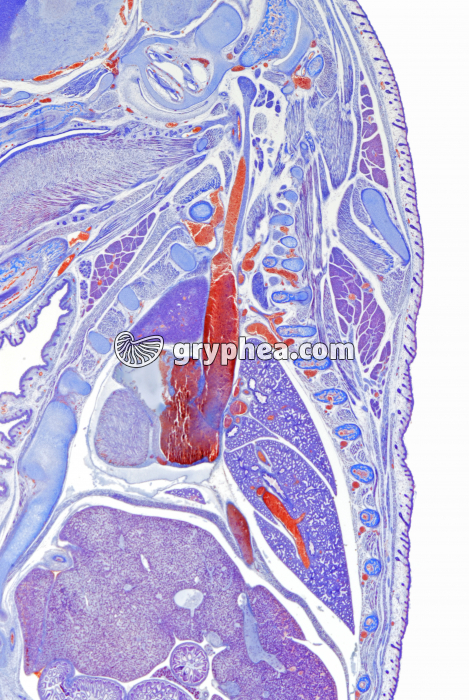

Embryon de Souris détail de la partie thoracique CL x3

Embryon de Souris détail de la partie thoracique CL x3 - gryphea.com